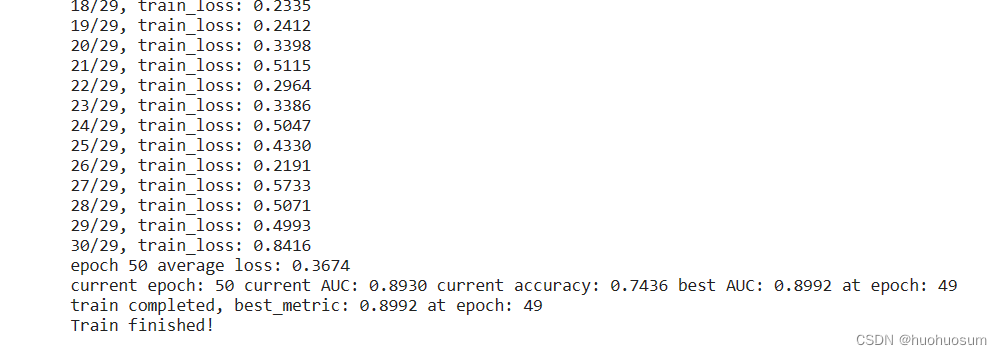

模型训练结果如图所示: